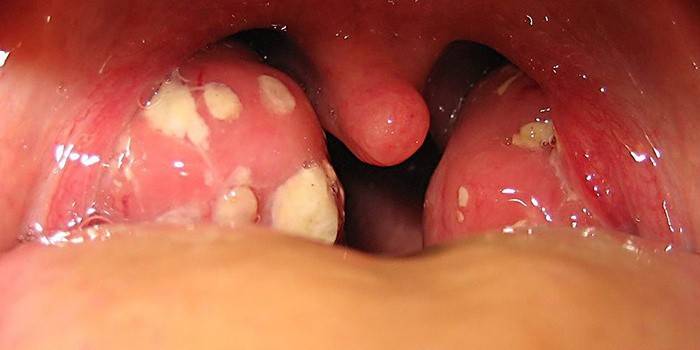

Kiedy odwiedzasz terapeuty podczas przeziębienia lub grypy, zawsze prosi on o otwarcie szeroko ust. Więc bada jamę i błonę śluzową gardła, co może wskazywać na obecność powiększonych migdałków. Zapalenie migdałków zwane jest również zapaleniem migdałków, które pojawia się w związku z powikłaniami po bólu gardła. W przypadku wykrycia objawów tej choroby pacjentowi natychmiast przepisuje się leczenie obejmujące płukanie, przyjmowanie leków i regularne badanie przez specjalistę.

Zapalenie migdałków lub stan zapalny migdałków ma pewne objawy, które są bardzo podobne do objawów bólu gardła. Według nich można niezależnie określić obecność stanu zapalnego w gruczołach:

- ostra postać zapalenia migdałków;

- biała powłoka na języku;

- ból gardła podczas połykania;

- migrena

- wysoka gorączka;

- obrzęk węzłów chłonnych na szyi;

- nieświeży oddech;

- utrata głosu.